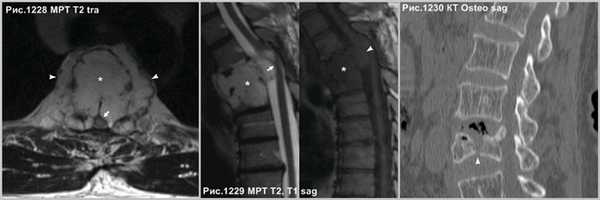

Осложнение в развитии гемангиом в виде экспансивного роста, что встречается не часто, когда опухоль (звёздочки на рис.1228,1229) распространяется за пределы тела позвонка (головки стрелок на рис.1228,1229), приводит к компрессии спинного мозга (стрелки на рис.1228, 1229). Серьёзное осложнение представляет собой патологический перелом тела позвонка (головки стрелки на рис.1230), структура которого была ослаблена разряжением губчатого вещества в процессе роста гемангиомы.

![]()

В случае нахождения гемангиомы в дужке или распространения с тела в дужку позвонка (головки стрелок на рис.1231-1233), важно указывать данный факт в связи с тем, что структура позвонка в указанном месте ослаблена и может послужить причиной патологического перелома в процессе медицинских манипуляций, так же важно учитывать этот факт нейрохирургам при транспедикулярной фиксации.